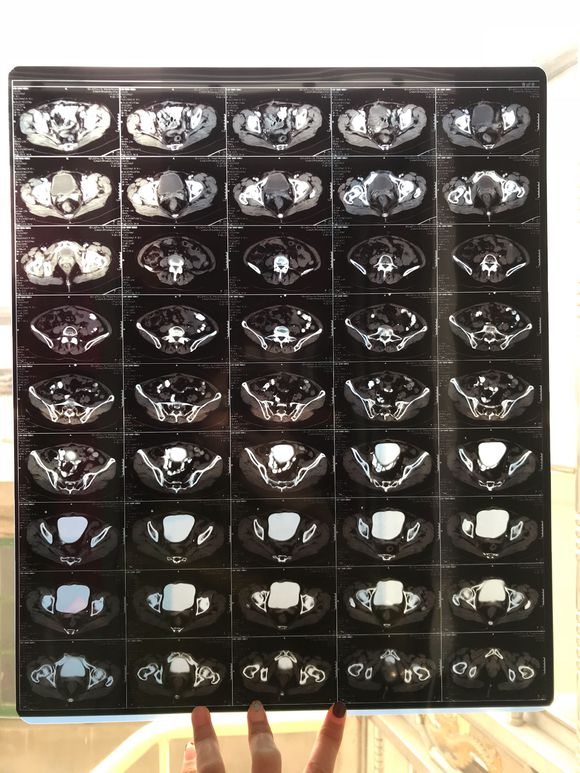

和你的故事 02019-04-09 患者家属我妈妈的病理结果报告,3期c1,大家可以帮忙看看吗,跪求了!我很急,谢谢!想知道是否严重,目前等术后出院后去肿瘤医院...

0人关注 4个回复 3521次浏览 -